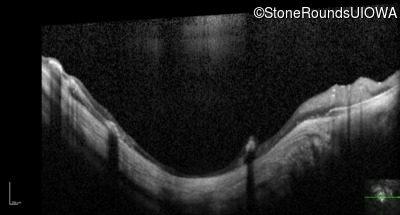

Optical Coherence Tomography - Right - 5/200 sc

Exemplar / OCT Stack

OCT Stack

Optical Coherence Tomography - Left - Hand Motion sc